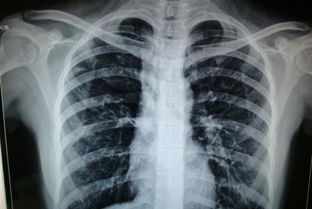

胸透可以看到胸部的軟組織、骨骼(包括胸椎)、縱隔(心臟、大血管、氣管、食管等)、氣管和支氣、胸膜、肺組織等??梢栽\斷肺和氣管的先天性疾病,如發(fā)育異常、肺部的各種炎癥、急慢性支氣管炎、比較明顯的支氣管擴張癥、肺氣腫或肺水腫、各型肺結核、肺腫瘤、胸腔積液、氣胸、縱隔腫瘤、心臟形態(tài)異常等

健康查體最常做的是胸部的X線檢查,最基本的就是胸透。 胸透可以看到胸部的軟組織、骨骼(包括胸椎)、縱隔(心臟、大血管、氣管、食管等)、氣管和支氣、胸膜、肺組織等。

可以診斷肺和氣管的先天性疾病,如發(fā)育異常、肺部的各種炎癥、急慢性支氣管炎、比較明顯的支氣管擴張癥、肺氣腫或肺水腫、各型肺結核、肺腫瘤、胸腔積液、氣胸、縱隔腫瘤、心臟形態(tài)異常等。